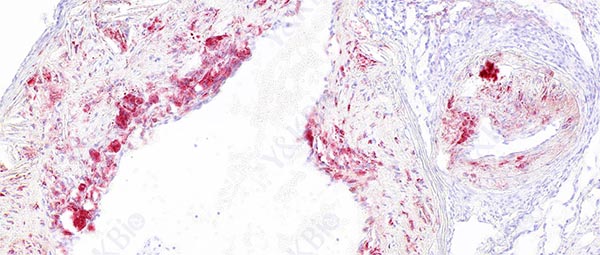

冰冻切片是一种常见的组织学技术,用于制备组织标本以供显微镜观察。为了预防冰晶形成,可以采取的措施包括适当固定组织、适当处理组织、使用适当的冷冻介质、控制切片速度、注意环境温度和湿度等。